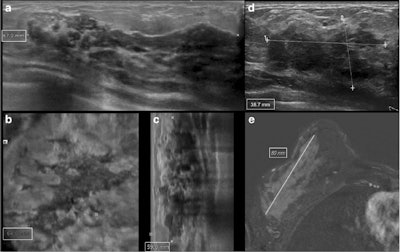

Conventional ultrasound is faster, cheaper, and more available but, as per usual, is operator-dependent. ABVS overcomes these limitations by providing a sonographic 3D representation of the breast tissue, with the advantage of multiplanar reformations and the capability of reviewing images retrospectively once the examination has been acquired. The device has a linear 5- to 14-MHz transducer mounted on a flexible arm with an automated one-button pressure and locking mechanism to speed and simplify the acquisition technique. The transducer scans volume slabs of up to 15.4 x 16.8 x 6 cm while acquiring 0.5-mm thick images in the transverse plane. Different preset cup sizes determined an automatic adjustment of depth, focal zone placement, overall gain, and frequency.

They retrospectively included 98 women with 100 index cancers who had undergone ultrasound (iU22, Philips Healthcare or Logiq E9, GE Healthcare) and ABVS (Acuson S2000, Siemens Healthineers), followed by 1.5-tesla MRI (Magnetom Avanto, Siemens or Magnetom Aera, Siemens). Images were interpreted by a pool of readers reporting lesion size, location, and BI-RADS features.